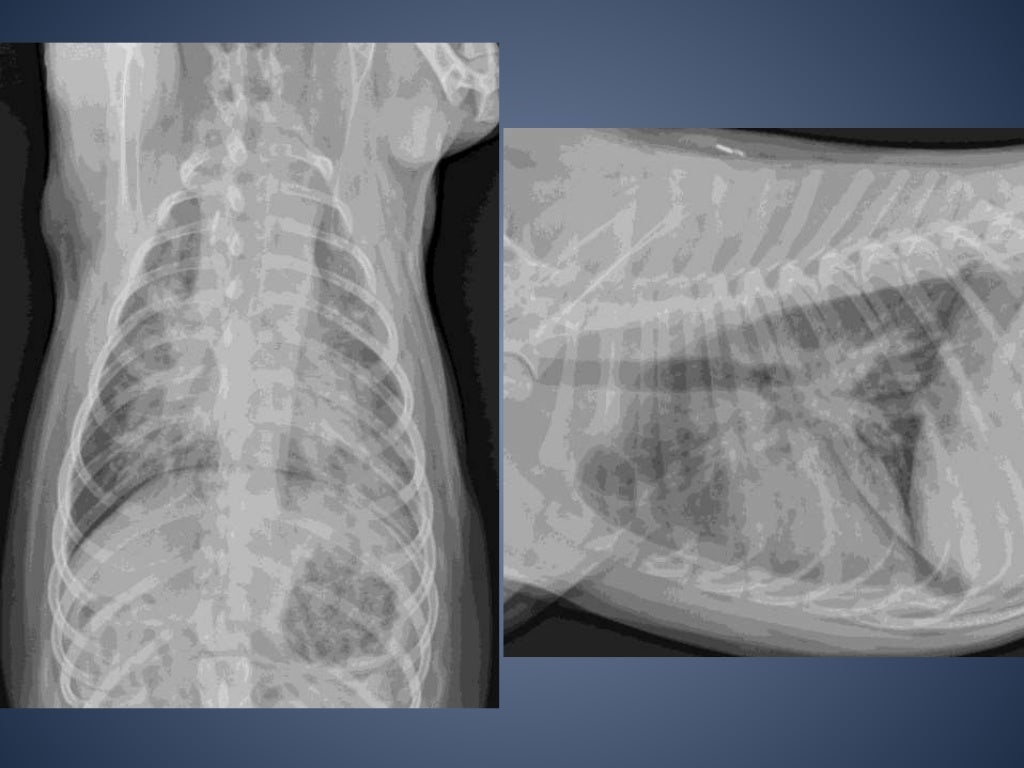

From www.mspca.org

Radiographic Approach to the Coughing Pet • MSPCAAngell Kennel Cough Xray The prominent clinical sign of kennel cough is a cough that sounds like a goose honk that may be followed by retching and gagging. Tracheobronchitis is usually suspected whenever a dog demonstrates the distinctive harsh cough and has a history of exposure to other susceptible or affected dogs. There’s a good chance they’re suffering from an upper respiratory infection. Find. Kennel Cough Xray.

Radiographic Approach to the Coughing Pet • MSPCAAngell Kennel Cough Xray The prominent clinical sign of kennel cough is a cough that sounds like a goose honk that may be followed by retching and gagging. Signs of systemic illness (eg, lethargy, decreased appetite). In a coughing pet, the recommended screening tests could include a complete blood count, serum biochemistry profile, urinalysis, parasite tests,. Thoracic radiographs are recommended for any patient with:. Kennel Cough Xray.